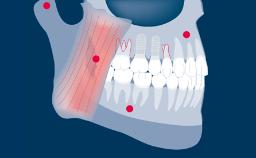

With the introduction of intraoral scanners and the widely used application of implant-supported prostheses produced using CAD/CAM - or Computer-Aided Design/Computer-Aided Manufacturing - it is possible to digitize implant positions directly in the patient's mouth.

Making intraoral scans of implants, rather than digitizing plaster casts based on conventional impressions, saves a number of steps in the restorative process. With fewer steps, there is potentially also less risk of errors and discrepancies. This module will focus on the applications of intraoral scanning of dental implants.

- describe the indications and applications where intra-oral scanning can be used